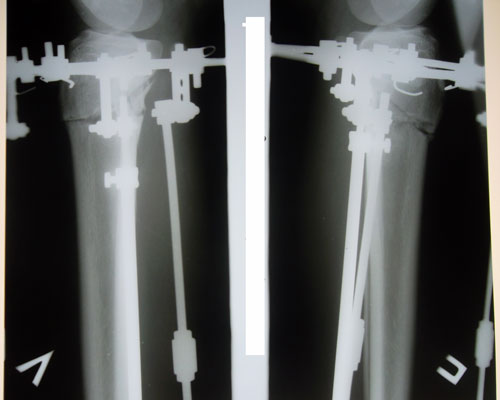

рентген в 16 дней после операции